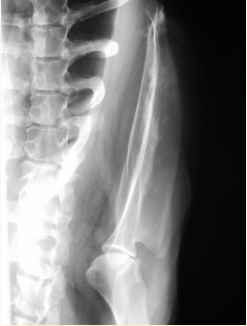

Humero:

Fracturas es lo mas comun, sobre todo en espiral. Pueden tener lesiones neuronales recuperables

Los sarcomas aparecen lejos del codo en extermidades anteriores y cerca de la rodilla en extermidades posteriores.

Las neoplasias sueln ser en la zona proximal del humero